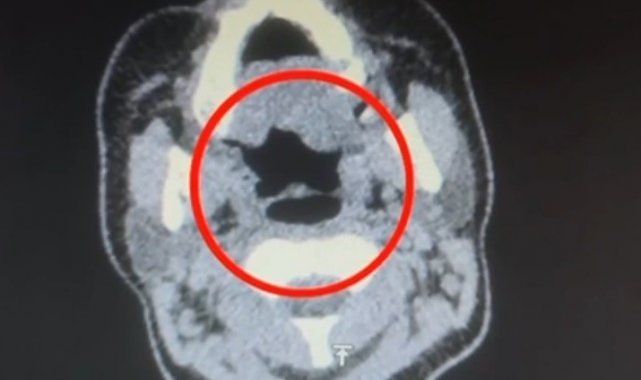

Kayseri İl Emniyet Müdürlüğü Narkotik Suçlarla Mücadele Şube Müdürlüğü ekipleri, uluslararası uyuşturucu madde ticareti yapan kurye şahıslara yönelik operasyon düzenledi. Operasyonda A.R.'yi (27) gözaltına alan ekipler, şahsı hastane muayenesine götürdü. Şüphelinin yapılan iç beden muayenesinde, mide kısmında bulunduğu tespit edilen 50 adet kapsül şeklinde toplam 500 gram uyuşturucu madde ele geçirildi.